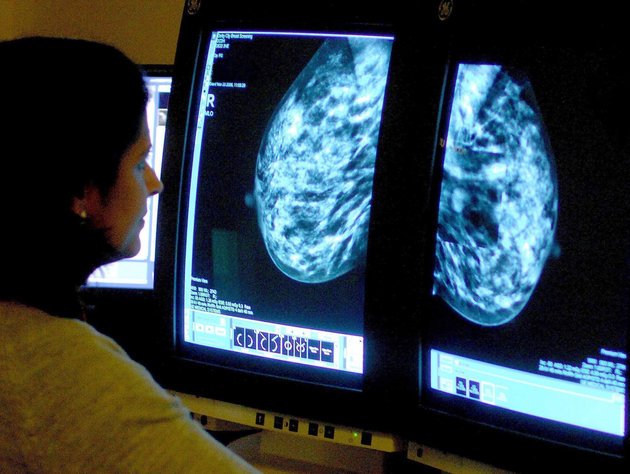

Some previous research said computer technology could serve almost as a second set of eyes for doctors. The technique uses special software to highlight suspicious-looking areas on mammogram images that radiologists who interpret the scans may have missed. The doctors then take another look before making a determination.

But some of these earlier studies involved adding computer detection to mammograms using outdated film X-rays, not more advanced digital X-rays now used in most mammograms nationwide, the study authors said. The older technique was more cumbersome; now computer-assisted detection is a standard part of digital mammogram machines.

The study involved nearly 324,000 women who had digital mammograms from 2003 to 2009. The researchers compared cancer detection rates after scans with and without computer-assisted detection. About 20 percent of scans did not include the technology.